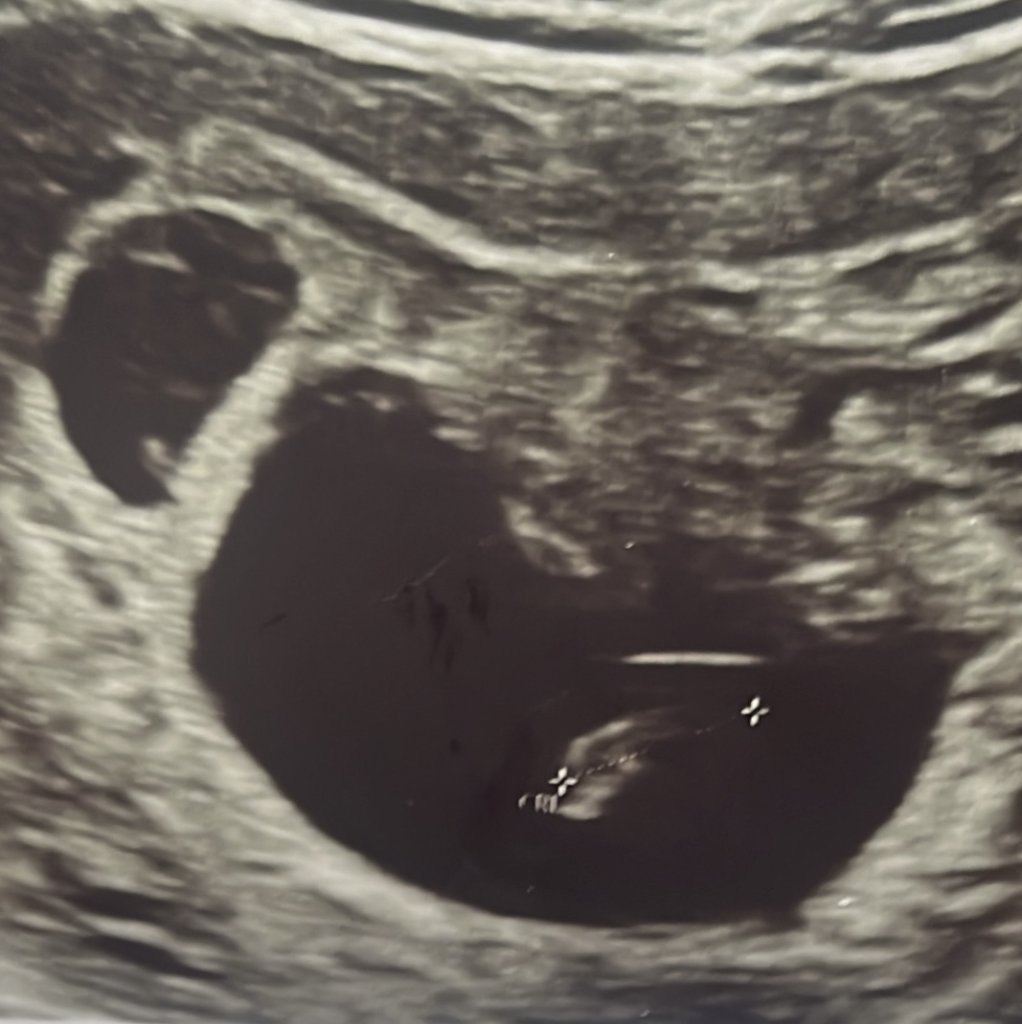

Herkese merhaba, doktor kontrolüme gittiğimde 7. Haftada ikiz bebek beklediğimizi öğrendik. Aralarında bir hafta olmasına rağmen birinin gelişimi gözle görülür derecede ufaktı. 9 gün sonra kontrolde bu bebeğimizin kalp atışının durduğunu öğrendik. Kendi kendine yok olmasını bekliyor doktorumuz. Bu durumu yaşayan arkadaşlarımız var mı? Kan sulandırıcı ve progestan kullanıyorum, doktorum devam etmemi söyledi. Bir de üstüne viral enfeksiyon olmuşum. Her şey üst üste geldi…